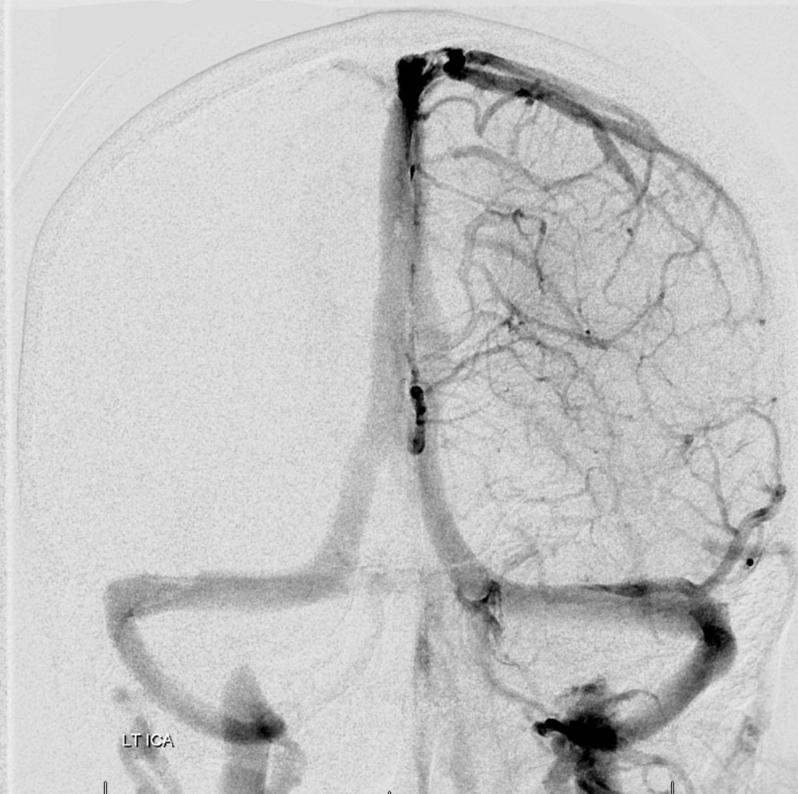

Following embolization, resection, recurrence (as frequently the case with childhood AVMs) and gamma-knife, things look good. Stereo, of course.

Following embolization, resection, recurrence (as frequently the case with childhood AVMs) and gamma-knife, things look good. Stereo, of course.